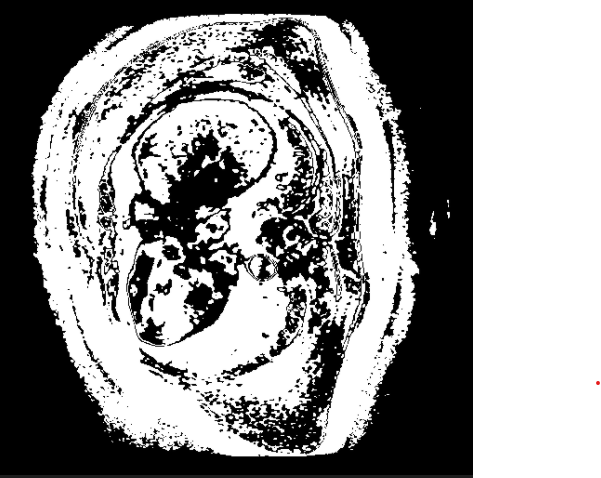

使用网上的大多数格式转换过来图像失真过于严重,出现了这种情况: